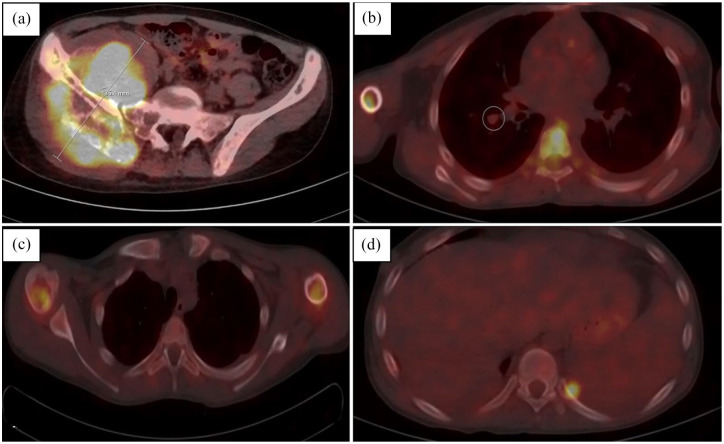

Case presentation: We present a case of 16-year-old patient with Ewing sarcoma diagnosed with neoplastic fever.